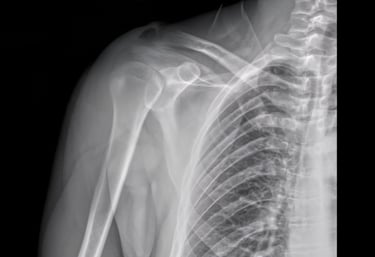

Shoulder X-rays

Advanced digital imaging for shoulder dislocations, rotator cuff concerns, and joint injuries. We deliver clear, detailed views for orthopedic evaluations and reporting.